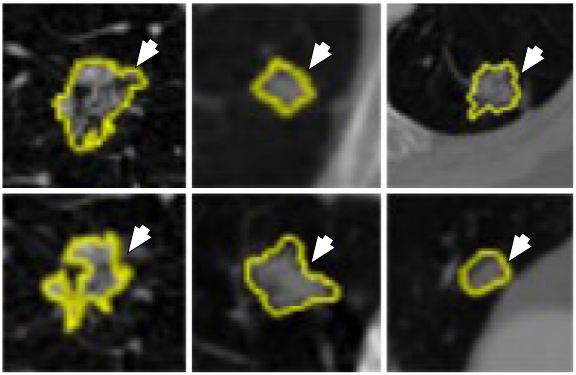

Lung cancer is a malignant disease with five year survival rate less than 20%, if not diagnosed early. Characterization of lung disease from CT images is difficult as small lung nodules are infrequently regarded malignant, difficult to biopsy and cannot be reliably characterized by positron emission tomography scan. DL-frameworks provided a new area of research in this field. In here for characterization of lung cancer (59), two DL-based frameworks are applied. Two separate characterizations were done using two DL techniques such as: CNN and DBN. It was found that CNN and DBN both gave better results than other conventional methods using feature extraction technologies. The pulmonary modules in lung could be diagnosed as malignant based on their shape which can be sphericity and speculation and composition of internal structures such as fluid, calcification and fat. In this paper, the chest CT images were collected from 1010 patients. The sensitivity of CNN and DBN was found to be 73.3% and 73.4% while specificity was found to be at 78.7% and 82.2%. The object process model of the system is given in Figure 34. The input CT images depicting various sizes of lung module is given in Figure 35. This application can be called as a ground level study of the use of DL for lung cancer detection. Multiple deeper layers could be added to improve accuracy. The paper lacked prevailing DL-based architectures.

Figure 35Different sizes of lung nodules (yellow) visualized in the CT images for characterization by the CNN and DBN (reproduced with permission from (55)).